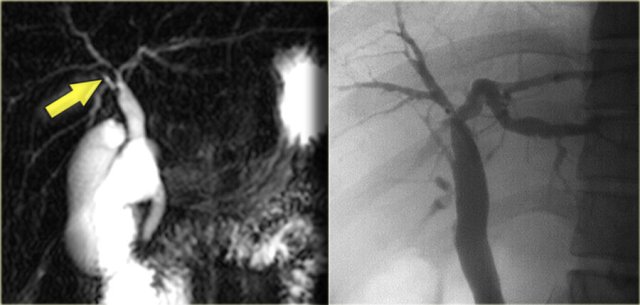

The cholangiogram is important in the work up of these patients, because obstruction has to be excluded.

This can be done with MRCP or ERCP, as is shown on the left.

There was no sign of obstruction.

The mild dilatation of the choledochal duct was the result of cholangitis.

Study the image on the left.

Then continue reading.

There is focal dilatation with intermixing strictures of the bile ducts in segment IV (arrow).

The other bile ducts and the choledochal duct are normal.

Cholangiocarcinoma can take on many forms in patients with Caroli disease.

The cholangiogram on the left demonstrates a focal stricture (blue arrow), which turned out to be a infiltrating cholangiocarcinoma.

The patient on the right has a cholangiocarcinoma in which the tumor was filling up the dilated ducts (yellow arrow).